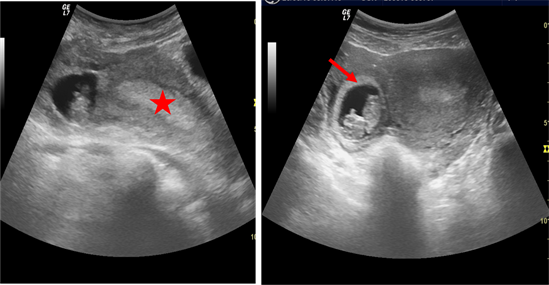

Bleeding from an ectopic pregnancy is the most dangerous cause of first trimester bleeding. It concerned 3.3% of the cases in our study. Belley and al found a rate of 5.2%. It occurs when the fertilized egg is implanted outside of the uterus, most often in the Fallopian tube. The ultrasonographic finding was the visualization of an annular adnexal mass containing a viable embryo or not (Figure 3), sometimes with a hemoperitoneum with an empty uterus [4] . The incidence is higher in patients with a history of prior ectopic pregnancy, previous pelvic inflammatory disease, tubal disease, presence of an intrauterine device, and in those undergoing in vitro fertilization [11] .

Figure 3. Abnormal location of the gestational sac (red arrow) in the right side of the empty uterus (red star).